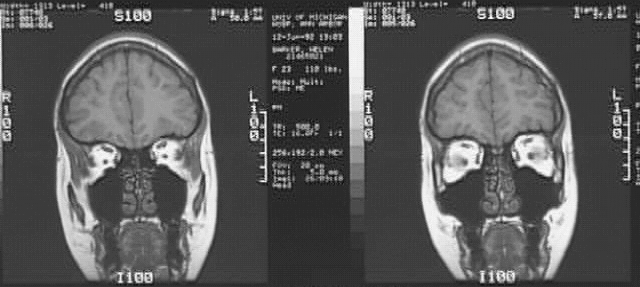

Radiology Images

Head & Neck: Head MRI 3 of 3: